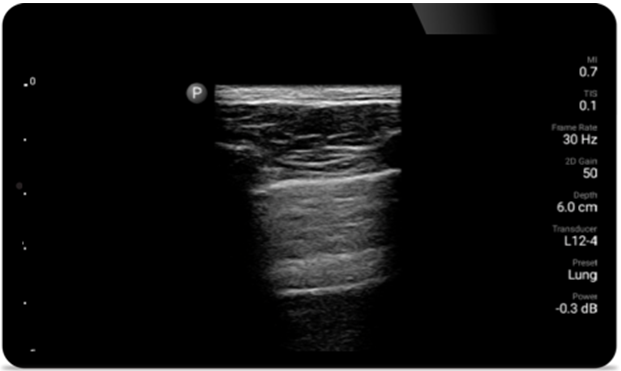

Korzystanie z systemu Lumify może przyczynić się do szybszej oceny pacjentów oraz lepszego diagnozowania najczęstszych przyczyn duszności i innych chorób płuc

• Rozszerzony zakres częstotliwości roboczej od 4 do 1 MHz • Obrazowanie 2D, kolorowy Doppler, tryb M-mode, zaawansowana technika XRES oraz wielowymiarowe obrazowanie harmoniczne • Obrazowanie w wysokiej rozdzielczości do badań jamy brzusznej i serca: optymalizacja ustawień predefiniowanych obrazowania serca, badań położniczo-ginekologicznych, płuc, jamy brzusznej oraz protokołu FAST System Lumify pomaga ratować życie w warunkach przedszpitalnych